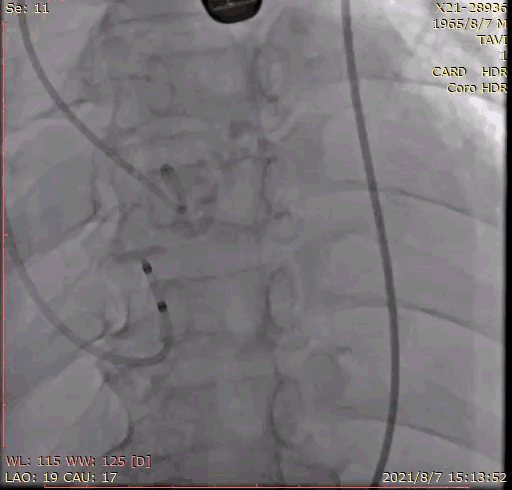

2.术前冠脉造影,提示左冠中段存在狭窄,TEE 见大量反流影;

6.经右桡动脉血管鞘送入6F JL4.0指引导管,送 Runthrough至前降支远端,后在GuidezillaII 支撑保护下送 4.0×18mm 支架至 LAD 近段;

7.根据术前评估及球囊预扩情况,选择 26mm 沛嘉 TaurusElite 瓣膜进行植入,第一次展开瓣膜位置偏下,全回收一次再次展开瓣膜,在 130 次/分快速起搏下释放瓣膜,同时将冠脉支架拉至左冠开口外约 9mm 处释放;